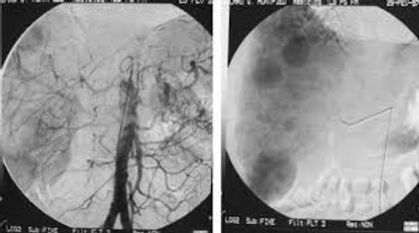

La chimioembolisation transartérielle

La chimioembolisation est indiquée pour les patients qui présentent plusieurs foyers tumoraux et / ou volumineux et qui ne peuvent bénéficier ni d’une transplantation, ni d’une chirurgie, ni d’un traitement par radiofréquence. La chimioembolisation transartérielle ou par voie artérielle consiste à délivrer directement au niveau du site tumoral à la fois des médicaments de chimiothérapie (pour détruire les cellules cancéreuses) et un produit dit « d’embolisation » liquide (lipiodol) ou solide (microbilles) qui bloque la circulation sanguine alimentant la tumeur en oxygène et en nutriments.